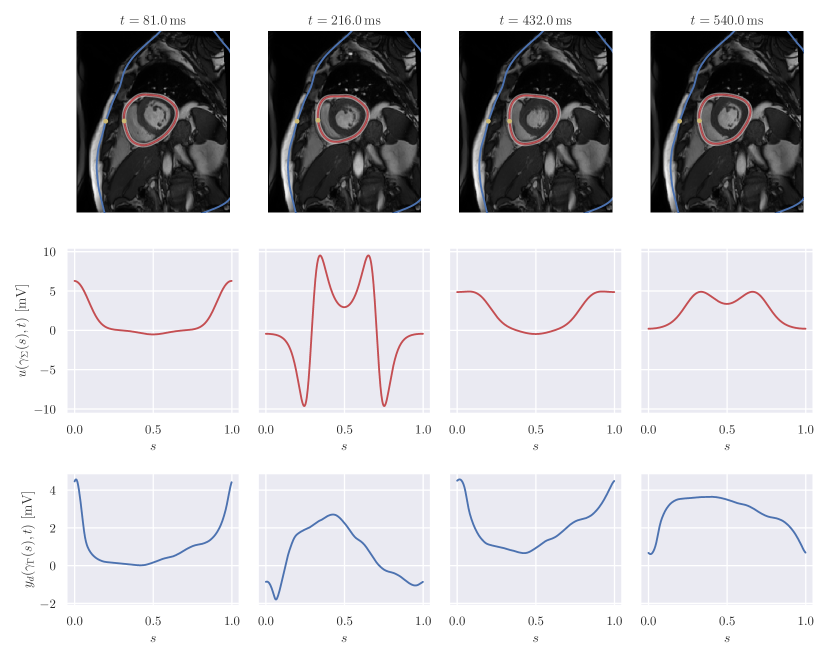

In this section we present numerical experiments to assess the validity of the approach. To obtain a space-time reference torso anatomy, we have segmented cardiac magnetic resonance (CMR) imaging data previously acquired [40]. The temporal image stack was obtained from a cine ECG-triggered segmented steady-state free precession sequence in mid-ventricular short-axis orientation. Slice thickness and voxel resolution were 8 mmtimes8millimeter8\text{\,}\mathrm{mm} and 1.36 mmtimes1.36millimeter1.36\text{\,}\mathrm{mm}, respectively. The 25-phase temporal stack covered the whole heart beat, with an RR interval on the surface ECG of T=690 ms𝑇times690millisecondT=$690\text{\,}\mathrm{ms}$). Images were reordered such that the first image at t=0 ms𝑡times0millisecondt=$0\text{\,}\mathrm{ms}$ corresponded to the diastole, defined by the maximal left ventricular cavity volume. The systole, defined by the minimum cavity volume, occurred at t=270 ms𝑡times270millisecondt=$270\text{\,}\mathrm{ms}$. The segmentation was performed by manual contour tracing of the epicardium for each image. In order to end up with a smooth computational domain, we performed a least-squares fit of the contours using a truncated Fourier series with a threshold of 103superscript10310^{-3} in the relative root-mean-square error. Finally, we interpolated the extracted shapes to get a pericardial representation at 50 time instants. The chest was also previously segmented from ultra-fast gradient-echo “VIBE” images in axial, coronal, and sagittal orientations to produce a smooth 3-dimensional closed surface modelled in Blender222https://www.blender.org. As shown in Figure 1, the contour of the chest was eventually obtained by intersecting the chest surface with the orientation plane of the pericardium.

Refer to caption

Figure 2: Geometry and input data. First row: CMR images with superimposed segmented chest (blue) and time-dependent pericardium (red). The shaded region around the pericardium represents the shape confidence interval, obtained as 𝔼[Σ](t)±1.96StdDev[Σ](t)plus-or-minus𝔼delimited-[]Σ𝑡1.96StdDevΣ𝑡\mathbb{E}[\Sigma](t)\pm 1.96\cdot\operatorname{StdDev}[\Sigma](t). The yellow dots correspond to γΓ(0)subscript𝛾Γ0\gamma_{\Gamma}(0) and γΣref(t)(0)subscript𝛾subscriptΣref𝑡0\gamma_{\Sigma_{\mathrm{ref}}(t)}(0). Second row: forward data u(γΣ(s),t)𝑢subscript𝛾Σ𝑠𝑡u\big{(}\gamma_{\Sigma}(s),t\big{)}. Third row: inverse data yd(γΓ(s),t)subscript𝑦dsubscript𝛾Γ𝑠𝑡y_{\text{d}}\big{(}\gamma_{\Gamma}(s),t\big{)}.

In Figure 2, we summarised the input data for the forward and inverse problem and the geometry of the pericardium, superimposed with the CMR images. To model the uncertainty, we selected the resulting reference shape of the pericardium Σref(t)subscriptΣref𝑡\Sigma_{\text{ref}}(t), for t[0,T)𝑡0𝑇t\in[0,T), as the space-time mean of the random deformation field 𝝌𝝌\bm{\chi}. The covariance of 𝝌𝝌\bm{\chi} evaluated at the points 𝐳^=(𝐱^,t)^𝐳^𝐱𝑡\hat{\bf z}=(\hat{\bf x},t) with 𝐱^Σref(t)^𝐱subscriptΣref𝑡\hat{\bf x}\in\Sigma_{\text{ref}}(t) and 𝐳^=(𝐱^,t)superscript^𝐳superscript^𝐱superscript𝑡\hat{\bf z}^{\prime}=(\hat{\bf x}^{\prime},t^{\prime}) with 𝐱^Σref(t)superscript^𝐱subscriptΣrefsuperscript𝑡\hat{\bf x}^{\prime}\in\Sigma_{\text{ref}}(t^{\prime}) was the product of a matrix-valued kernel in space and a scalar kernel in time. For the spatial component of the covariance, we considered the Matérn kernel

In the forward problem, the pericardial potential u(𝐱,t)𝑢𝐱𝑡u({\bf x},t) was defined analytically as a T𝑇T-periodic function in the variable t𝑡t. For convenience, we set u(𝐱,t)=u(γΣ(t,ω)(s),t)𝑢𝐱𝑡𝑢subscript𝛾Σ𝑡𝜔𝑠𝑡u({\bf x},t)=u\big{(}\gamma_{\Sigma(t,\omega)}(s),t\big{)}, being s[0,1)𝑠01s\in[0,1) the normalised curvilinear coordinate. We simulated a left bundle branch block, that is the extracellular potential consisted in a propagation from free wall of the right ventricle, at s=0𝑠0s=0, towards the free wall of the left ventricle, at s=0.5𝑠0.5s=0.5. The propagation took 150 mstimes150millisecond150\text{\,}\mathrm{ms}, consistent with a long QRS complex. The specific analytical form of u(𝐱,t)𝑢𝐱𝑡u({\bf x},t) is given in Appendix B.

To generate the input data for the inverse problem, we computed the solution of the forward problem on the space-time reference geometry and eventually added Gaussian noise with zero mean and variance 108superscript10810^{-8}, corresponding to a signal-to-noise ratio of approximately 46 dBtimes46decibel46\text{\,}\mathrm{dB}.